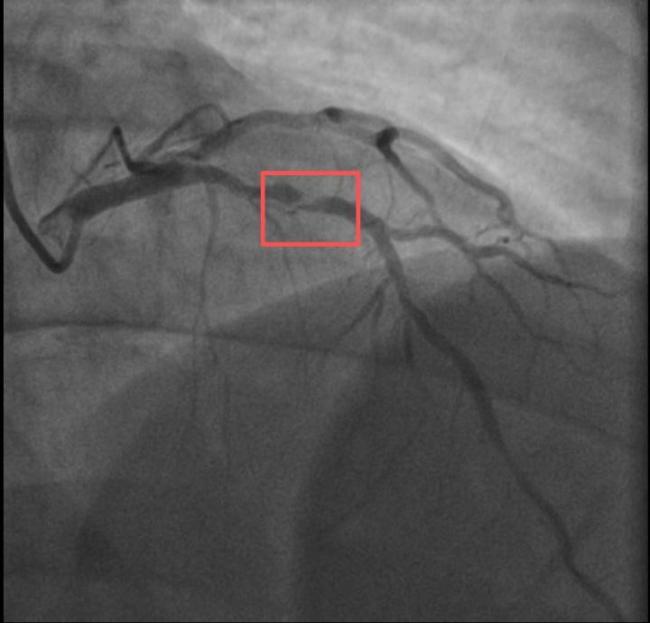

在2025年中国国际服务贸易交易会健康卫生服务专题展中,医疗领域国家人工智能应用中试基地成为焦点。近年来,国家大力推动人工智能的应用与发展,并将建设一批国家人工智能应用中试基地写入《关于深入实施“人工智能+”行动的意见》